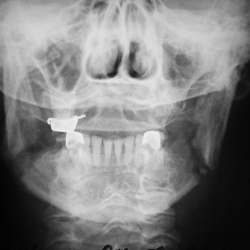

Женщина обратилась почти через месяц после неудачного тесного общения с собутыльником. Ох, стоматологи и ругались. Что делать, не знали, слишком дефекты большие, а хирургическое лечение при...